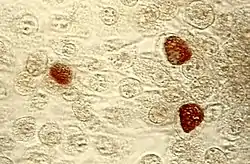

Under magnification of 50X, a McCoy cell monolayer culture, and that some of the cells exhibited Chlamydia trachomatis inclusion bodies. Using cell cultures from the McCoy cell line is one methods implemented in diagnosing Chlamydia infections.

Under magnification of 50X, a McCoy cell monolayer culture, and that some of the cells exhibited Chlamydia trachomatis inclusion bodies. Using cell cultures from the McCoy cell line is one methods implemented in diagnosing Chlamydia infections. Chlamydia trachomatis inclusion bodies (brown) in a McCoy cell culture

Chlamydia trachomatis inclusion bodies (brown) in a McCoy cell culture